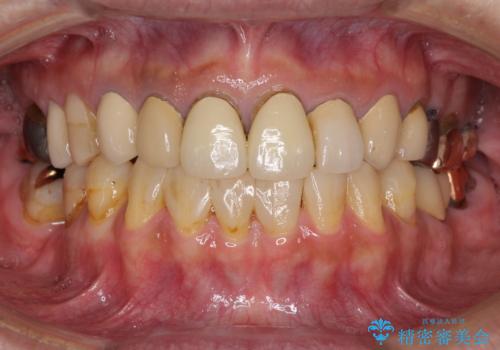

[ インプラント治療 ]失った奥歯を回復したい

![[ インプラント治療 ]失った奥歯を回復したいの症例 治療前](https://seimitsushinbi.jp/wp/wp-content/uploads/2021/11/036b501e44e72b51304eaa0dd62d1613-500x350.jpg?v=1637928855)